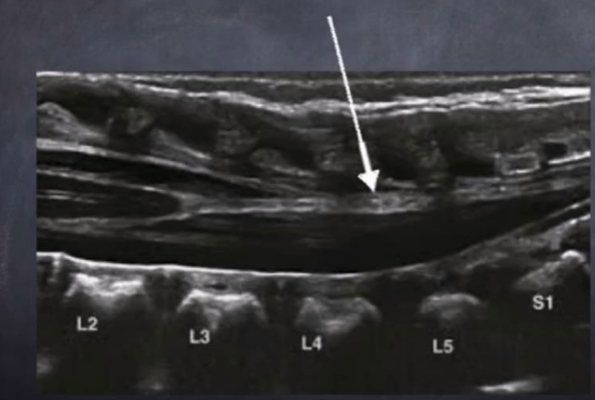

solid white arrow

echogenic epidural fat

vb

vertebral bodies

d

intervertebral disks

p

spinous processes

arrow

lumbosacral joint